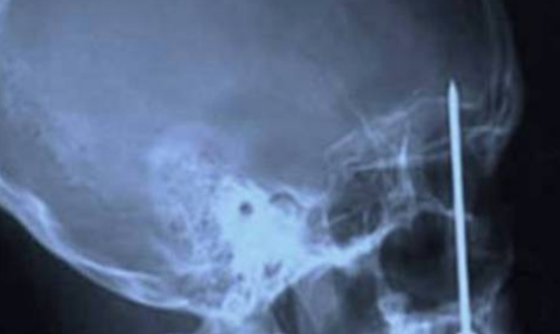

10、钥匙

x光片发现十大最恐怖的东西,你绝对想不到居然有它241 / 作者:UFO外星人爱好者 / 帖子ID:47859

这是怎么发生的?17个月大的尼古拉斯霍德曼被自己的妈妈用钥匙穿透了他的眼窝,刺入了他的头骨。幸运的是,他完全康复了。